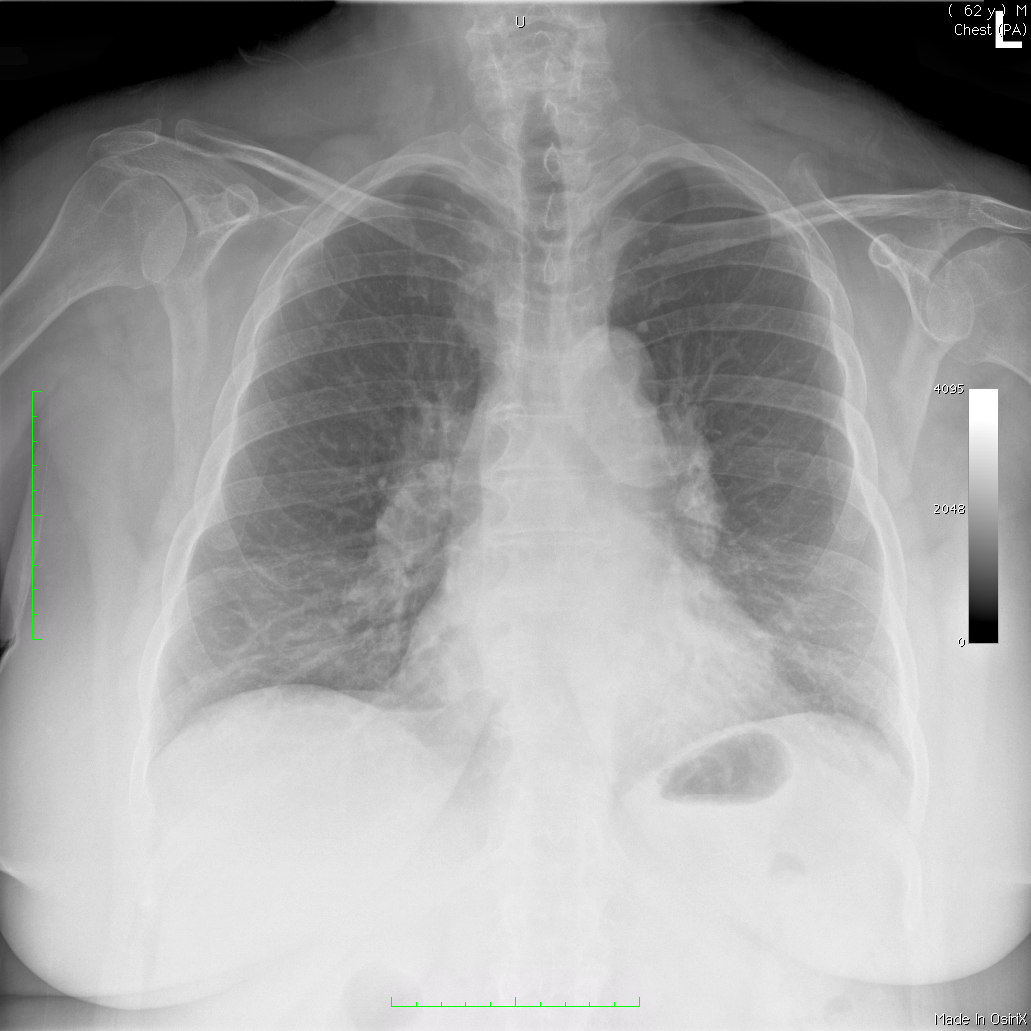

Topic 7

intermediate case for mediastinal widening

Further Explanation: